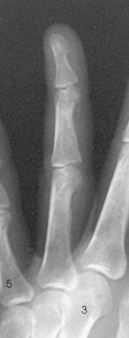

Structures shown: A lateral projection of the affected digit is shown (Figs. 4-24 through 4-27).

Structures shown: The resultant image shows a PA oblique projection of the bones and soft tissue of the affected digit (Figs. 4-32 through 4-35).

• With the digit under examination extended and other digits folded into a fist, have the patient’s hand rest on the lateral, or radial, surface for the second or third digit (Figs. 4-20 and 4-21) or on the medial, or ulnar, surface for the fourth or fifth digit (Figs. 4-22 and 4-23).

• Rest the second and fifth digits directly on the IR, but for an accurate image of the bones and joints, elevate the third and fourth digits and place their long axes parallel with the plane of the IR. A radiolucent sponge may be used to support the digits.